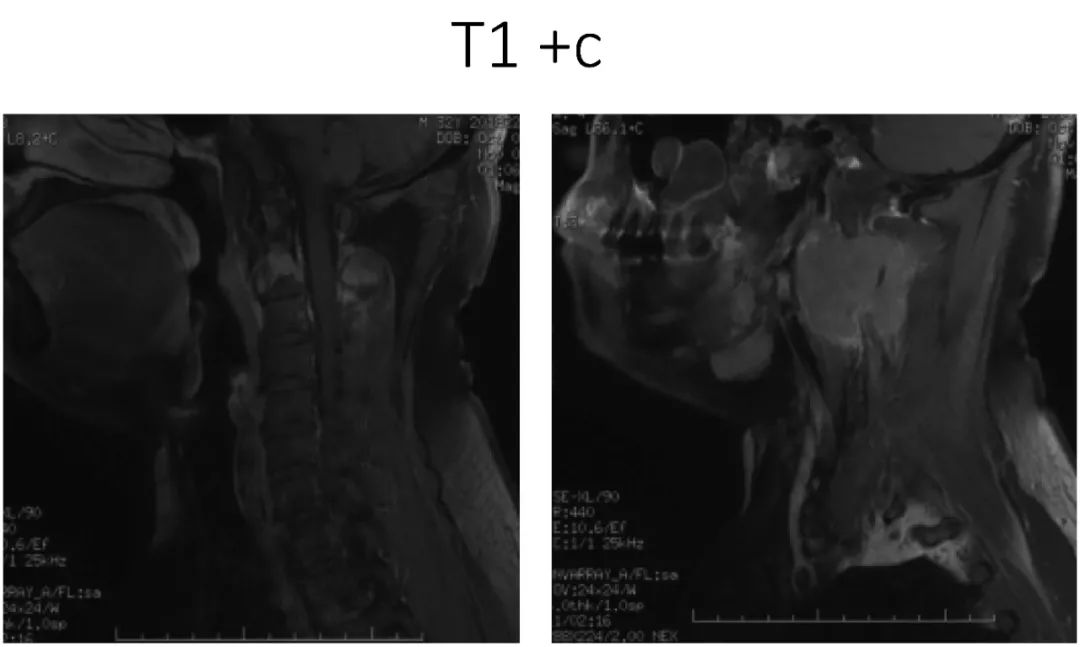

影像资料:

诊断:C2椎体肿瘤